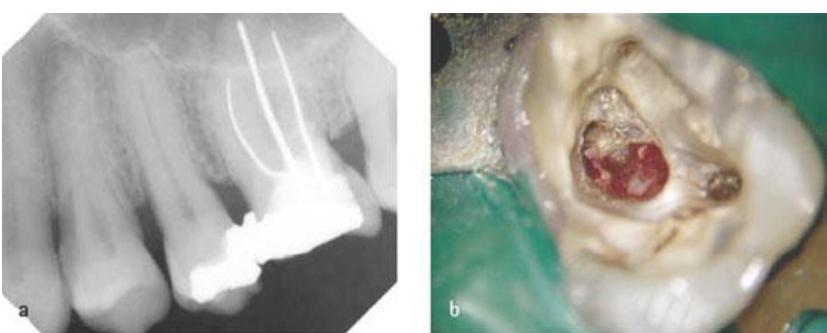

牙齿硬组织是由牙釉质、牙骨质和牙本质三部分构成的,内部的空腔称为髓腔。髓室底穿孔是由于龋坏、病理性吸收或牙髓治疗失误等原因造成的牙髓腔和牙周的病理性相通。髓室底就好比是一座房子的地基,髓室底穿孔了,就等于是地基漏了,危害可想而知。一旦髓室底穿孔了,穿孔地方的组织就可能引起炎症的反复发作,影响牙槽骨吸引,让患牙的正常功能难以发挥。如果不及时治疗,就会最终导致牙齿坏死、腐蚀、拔除。

在临床中,大多数医生遇到髓室底穿孔的患者,一般会建议拔除患病牙齿,即便当时选择做了充填补牙的解决办法,但最终还是难以避免拔牙这样的结果。这主要还是因为髓室底位置较深,而且隐蔽,穿孔修复时对修补材料要求极高,而诊疗医生因为视野受限,治疗难度也会大大增加,治疗效果也难以达到满意。

在治疗上,我们可以先对患牙进行修补,用修补穿孔的材料将穿孔处修复起来。近年来,由于各种生物相容性良好的修补材料的出现,明显改善了髓室底穿孔的修复治疗效果。比如MTA(矿物三氧化聚合体),它的生物相容性好,封闭性好,能促进硬组织的再生,并且没有神经毒性,是髓室底穿孔比较理想的修补材料。